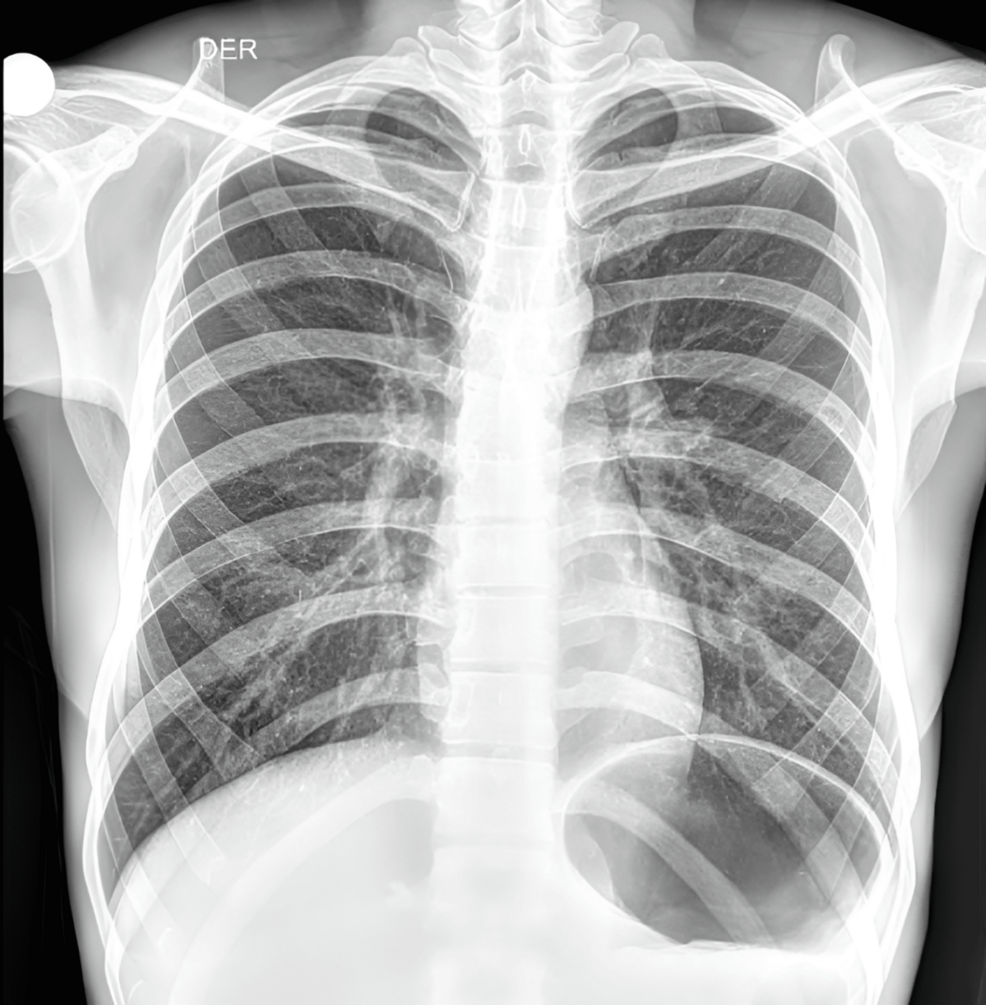

3. Imaging Studies (Ultrasound & CT Scan): A scrotal ultrasound showed evidence of epididymitis. A subsequent CT scan of the abdomen and pelvis revealed subtle inflammatory changes in the prostate gland and surrounding tissues.